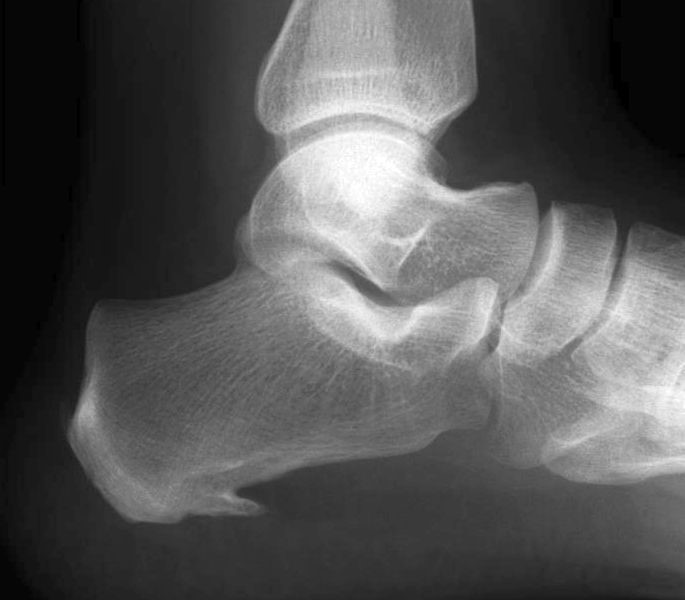

Orthosport2020-04-12T19:03:23+03:00Η κοτυλομηριαία πρόσκρουση ή «σύνδρομο πρόσκρουσης του ισχίου» εμφανίζεται συνήθως σε νεαρά άτομα και αποτελεί μία από τις αιτίες πρώιμων αρθριτικών αλλοιώσεων στην περιοχή του ισχίου. Χαρακτηρίζεται από την παθολογική επαφή της μηριαίας κεφαλής με την κοτύλη κατά τη διάρκεια συγκεκριμένων κινήσεων του ισχίου. Η επαφή αυτή έχει ως αποτέλεσμα την τριβή των δομών και [...]